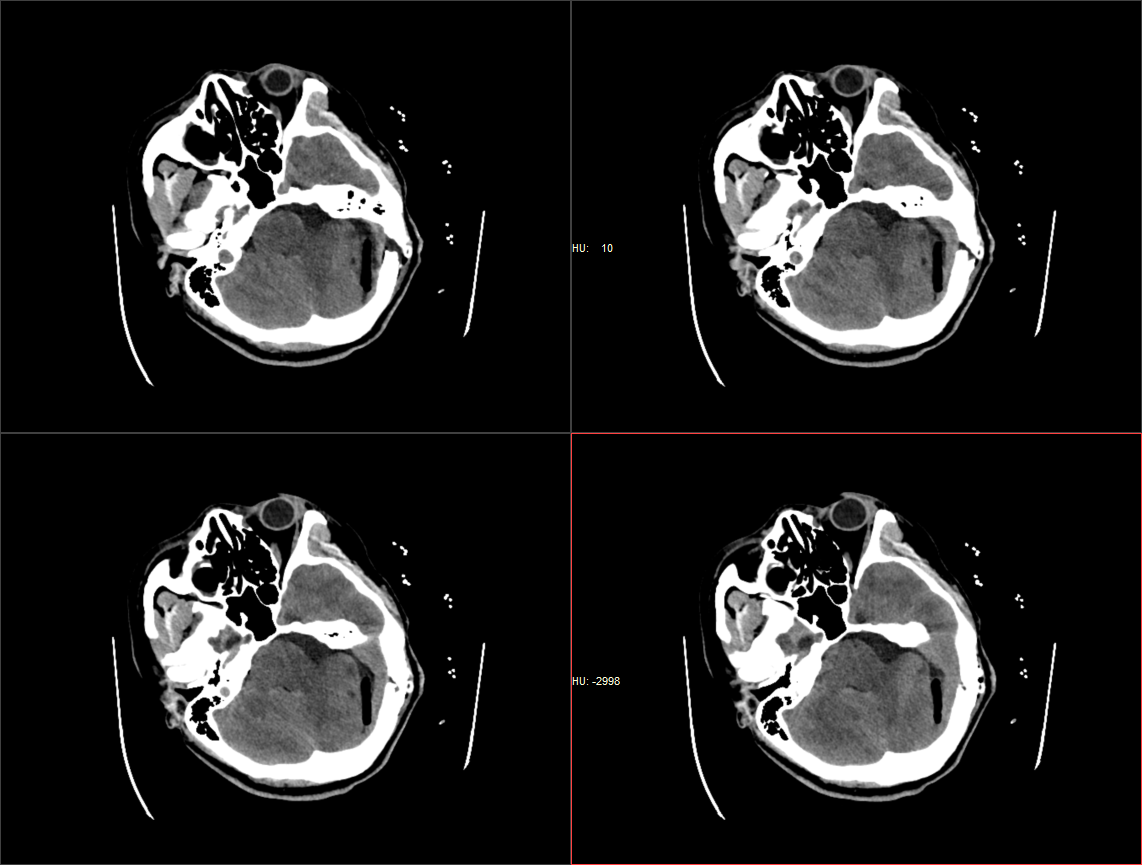

患者于入院前半年无明显诱因出现头痛、头晕,较剧烈,可耐受,无恶心、呕吐,无意识丧失,口服“止痛药(具体药名、剂量不详)”后症状稍缓解,入院前1周上述症状较前加重,患者前往当地医院就诊,行头颅MR示:1.左侧桥小脑角区占位,结合平扫及增强,现多考虑:皮样或表皮样囊肿。2。幕上梗阻性脑积水、脑室轻度积水。3.右侧上颌炎。现转至我院就诊。

术前影像: